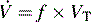

Ventilation

The process of gas movement in and out of the lungs is defined as ventilation. Minute ventilation (volume per minute image) is the product of respiratory frequency and tidal volume:

image